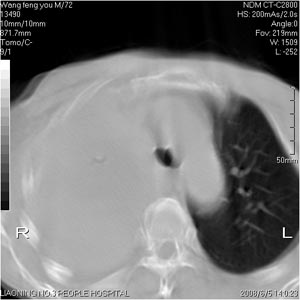

患者:男 72岁 右肩痛半年,近日来咳血,就诊.

右肺中心性肺癌伴骨,上纵膈淋巴节,胸腔转移

右肺上叶中心型肺癌伴肺不张、肋骨、肩胛骨、锁骨上淋巴结、右侧胸膜多发转移。

1.考虑:右肺上叶中央型肺癌并右肺上叶不张及右侧多发肋骨、上纵隔淋巴结及左肺转移。

2.右侧胸腔积液。